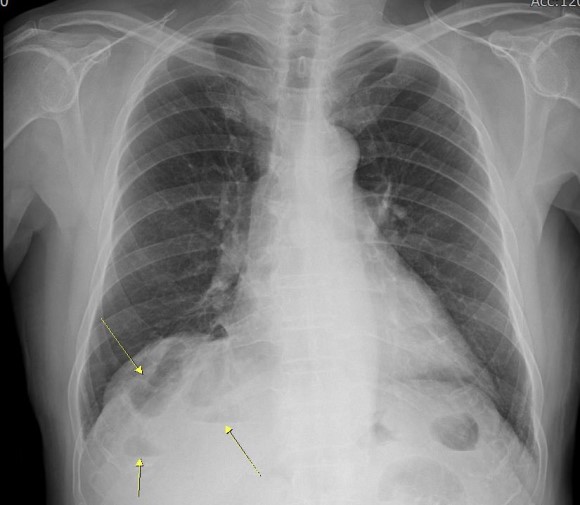

최근 이분의 여러 사진을 검토하는 과정에서 위 사진처럼 횡격막과 간 사이에 대장이 끼어 있는 것이 관찰되었으며, 이 마직막 사진에서는 그 부분의 대장에는 장의 약간의 마비를 시사하는 수면을 볼 수 있다.

이 분의 증상이 이른바 Chilaiditi 증후군이 아닐까 의심된다.이 분처럼 대장이 횡격막과 간 사이에 끼어 있는 현상을 Chilaiditisign이라고 한다. 이것이 확실한 증상을 가져온다는 것이 확인되면 Chilaiditi 증후군으로 진단한다. 그러나 이 병은 진단이 매우 어렵고 증상도 다양하다.

그러나 이처럼 대장이 치아에 끼어 보이는 경우는 비교적 적지 않고 만약 간경화가 심하면 간이 위축돼 이럴 수 있다며 이 현상을 보면 간질환을 의심해 볼 정도였다.